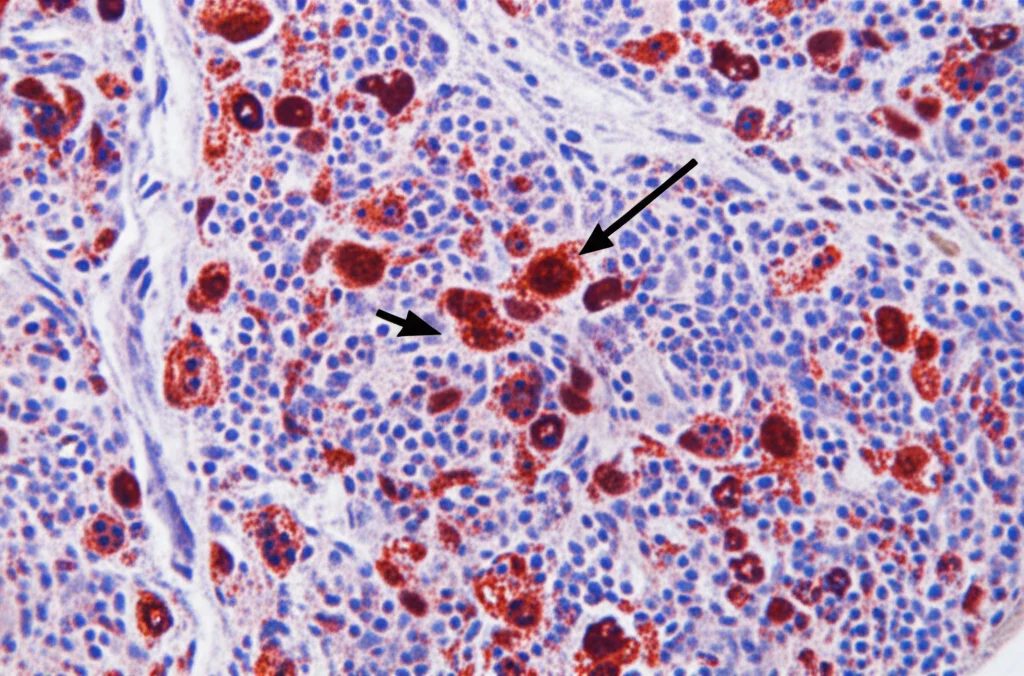

Ma la prova del nove è arrivata dall’immunoistochimica, usando un anticorpo (anti-CD15) che colora specificamente i neutrofili. Le immagini erano eloquenti: nei linfonodi dei controlli sani, i neutrofili erano praticamente assenti. Al contrario, nei linfonodi dei pazienti con artrite infiammatoria, si vedeva un chiaro afflusso di cellule CD15+!

La cosa ancora più interessante è che questa aumentata presenza di neutrofili è stata osservata sia nei pazienti con RA ACPA-positiva sia in quelli con IA ACPA-negativa (in particolare PsA e RA ACPA-negativa), rispetto ai controlli sani. C’era una certa variabilità tra i pazienti – alcuni ne avevano tantissimi, altri meno – ma il trend generale era chiarissimo e statisticamente significativo, specialmente per RA ACPA-positiva e PsA. Questa variabilità non sembrava legata a caratteristiche cliniche specifiche, all’età, al sesso o ai trattamenti in corso.